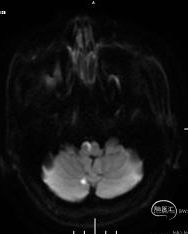

DWI示:延髓右侧、右侧小脑半球散在亚急性期梗死灶。